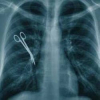

Железный желудок. Дональду Чарчу, попавшему в больницу по поводу опухоли в животе в больницу Сиэтла, опухоль удалили, но вместо нее оставили 35-сантиметровую железяку, которую вскоре увидели на рентгене. Железяку удалили, а ушлый американец договорился с госпиталем о компенсации в 97 тысяч долларов. Пресса тем временем наперебой публиковала дивные рентгеновские снимки.